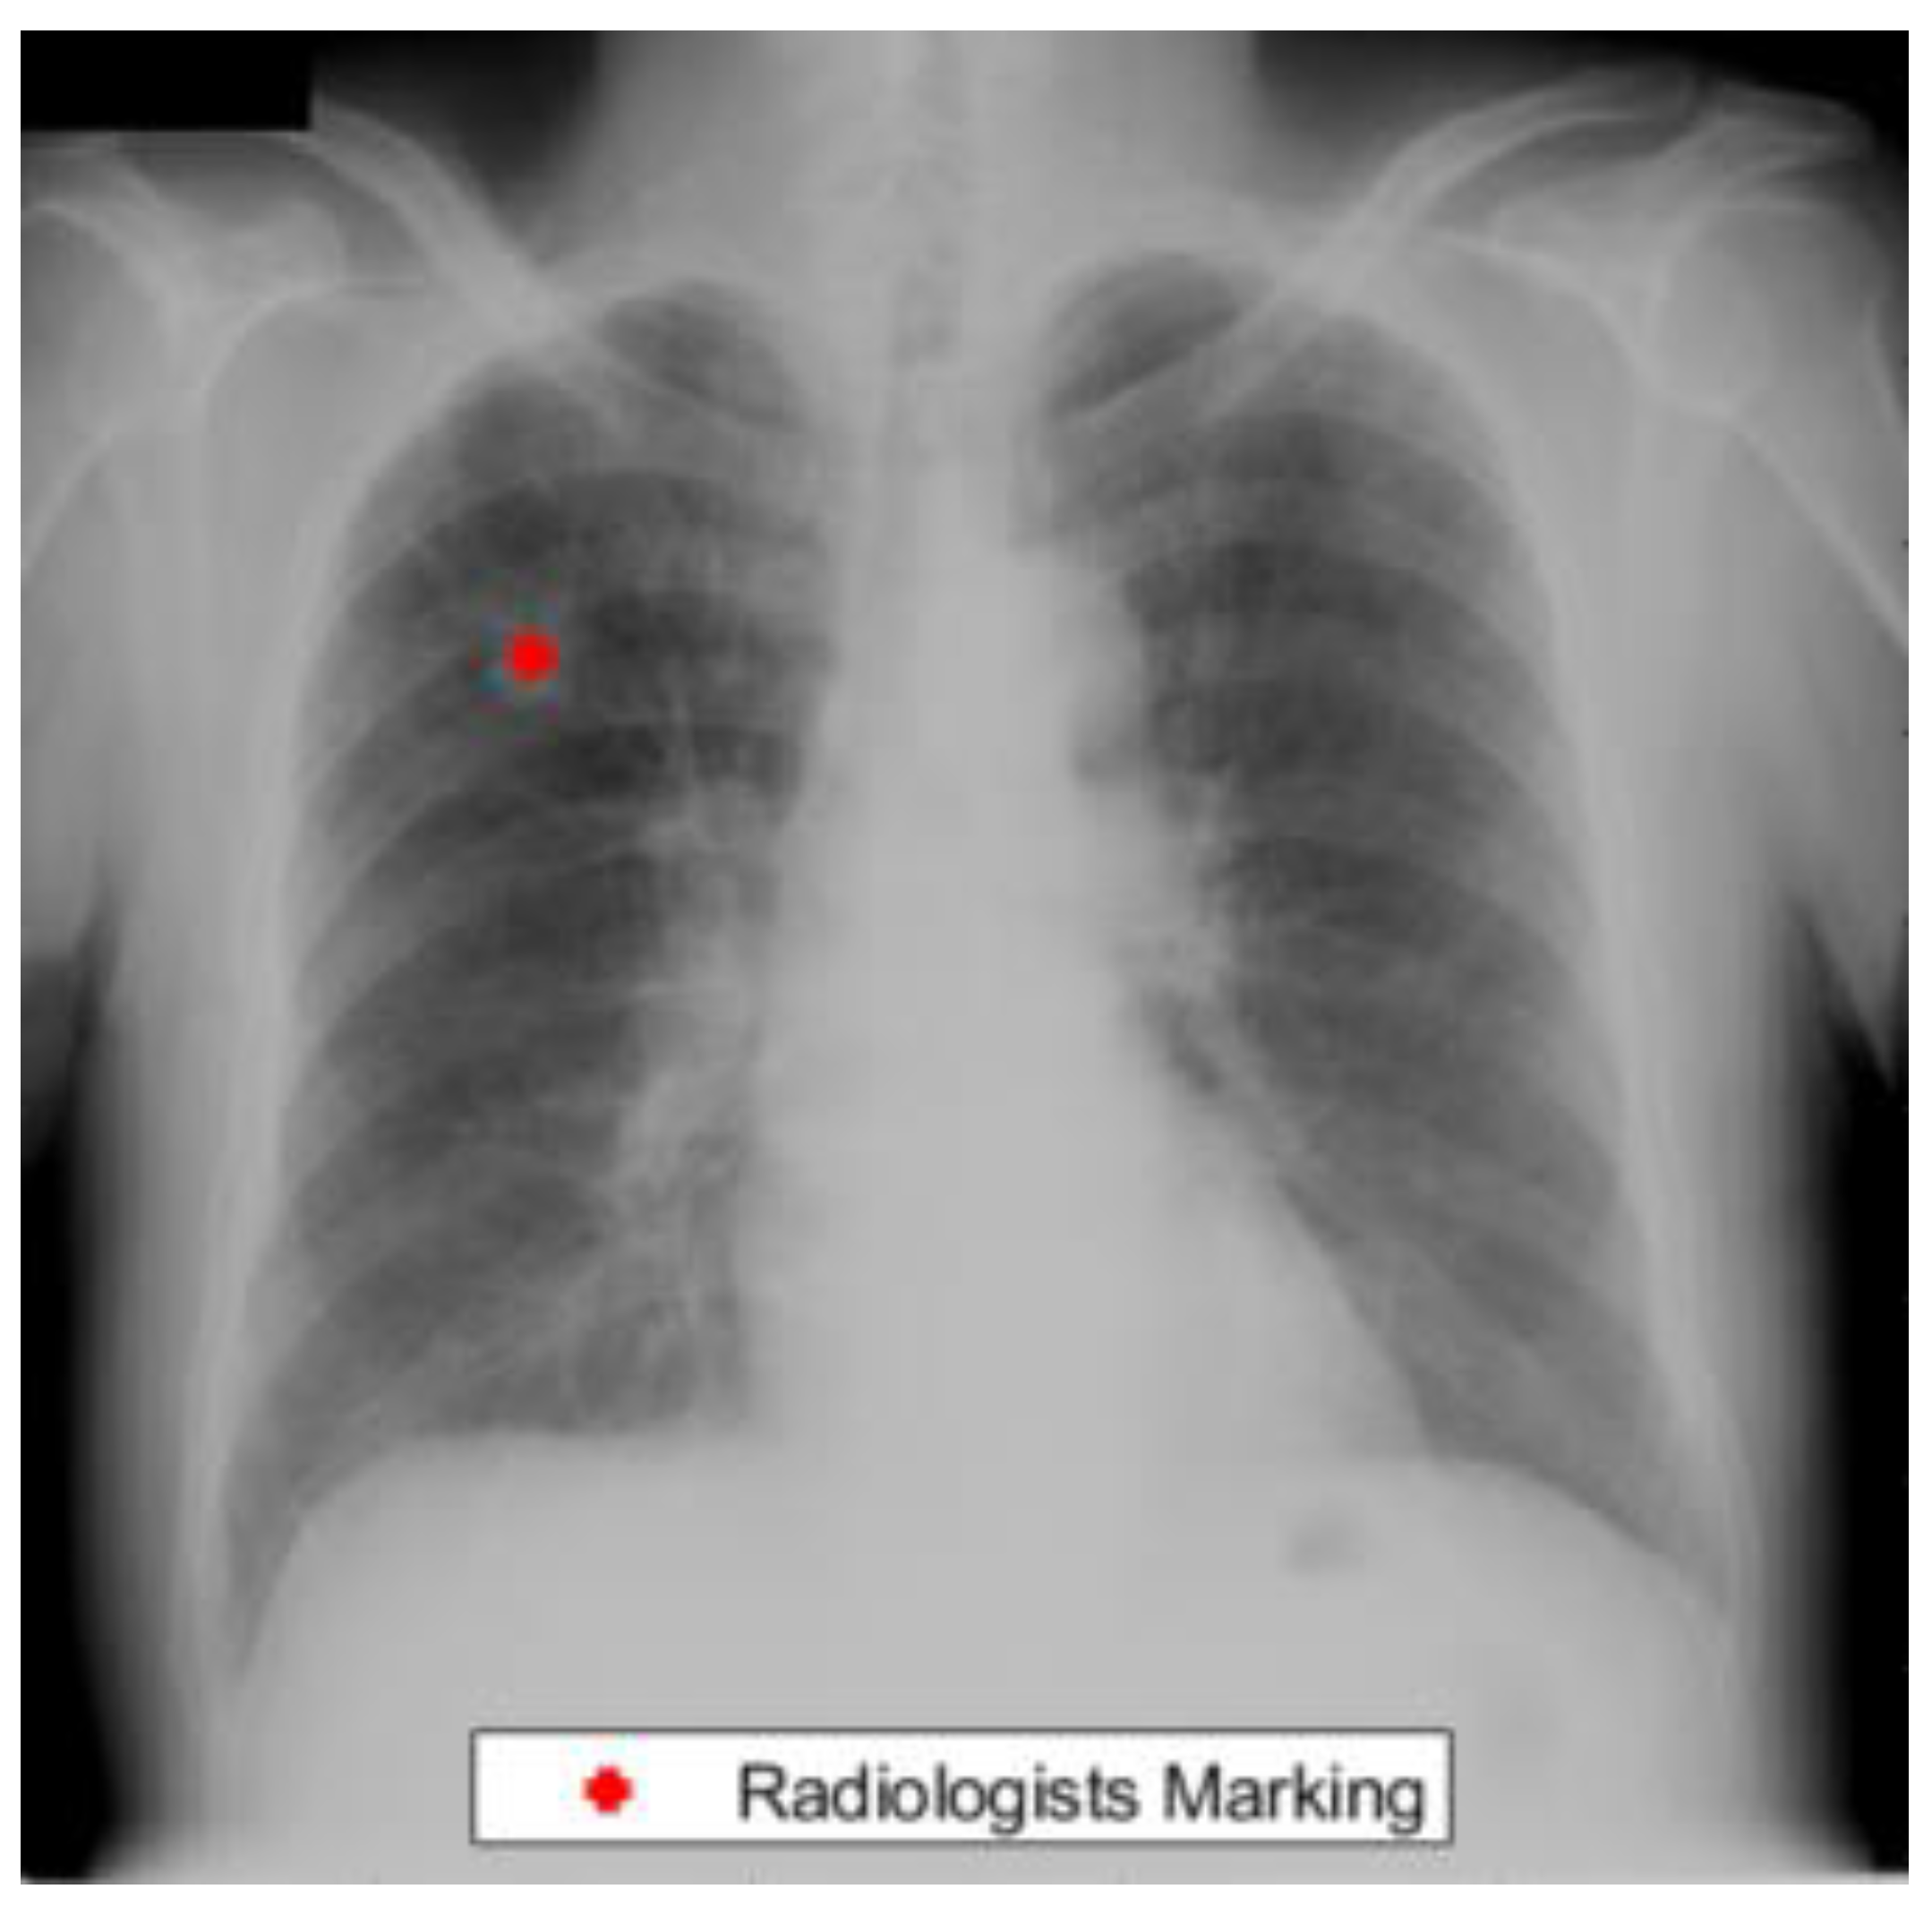

The Japanese Radiological Scientific Technology (JRST) dataset was marked by radiologists for the detection of lung nodules [42]. This dataset contained 247 chest radiographs out of which 154 cases contained nodule markings. In addition, lung masks are provided by [43] which can be used to study the performance of our lung segmentation algorithm. Figure 1 presents an example from the JRST dataset with a radiologist’s lung nodule marking.

Figure 1. An example from the JRST dataset with a radiologist nodule marking.